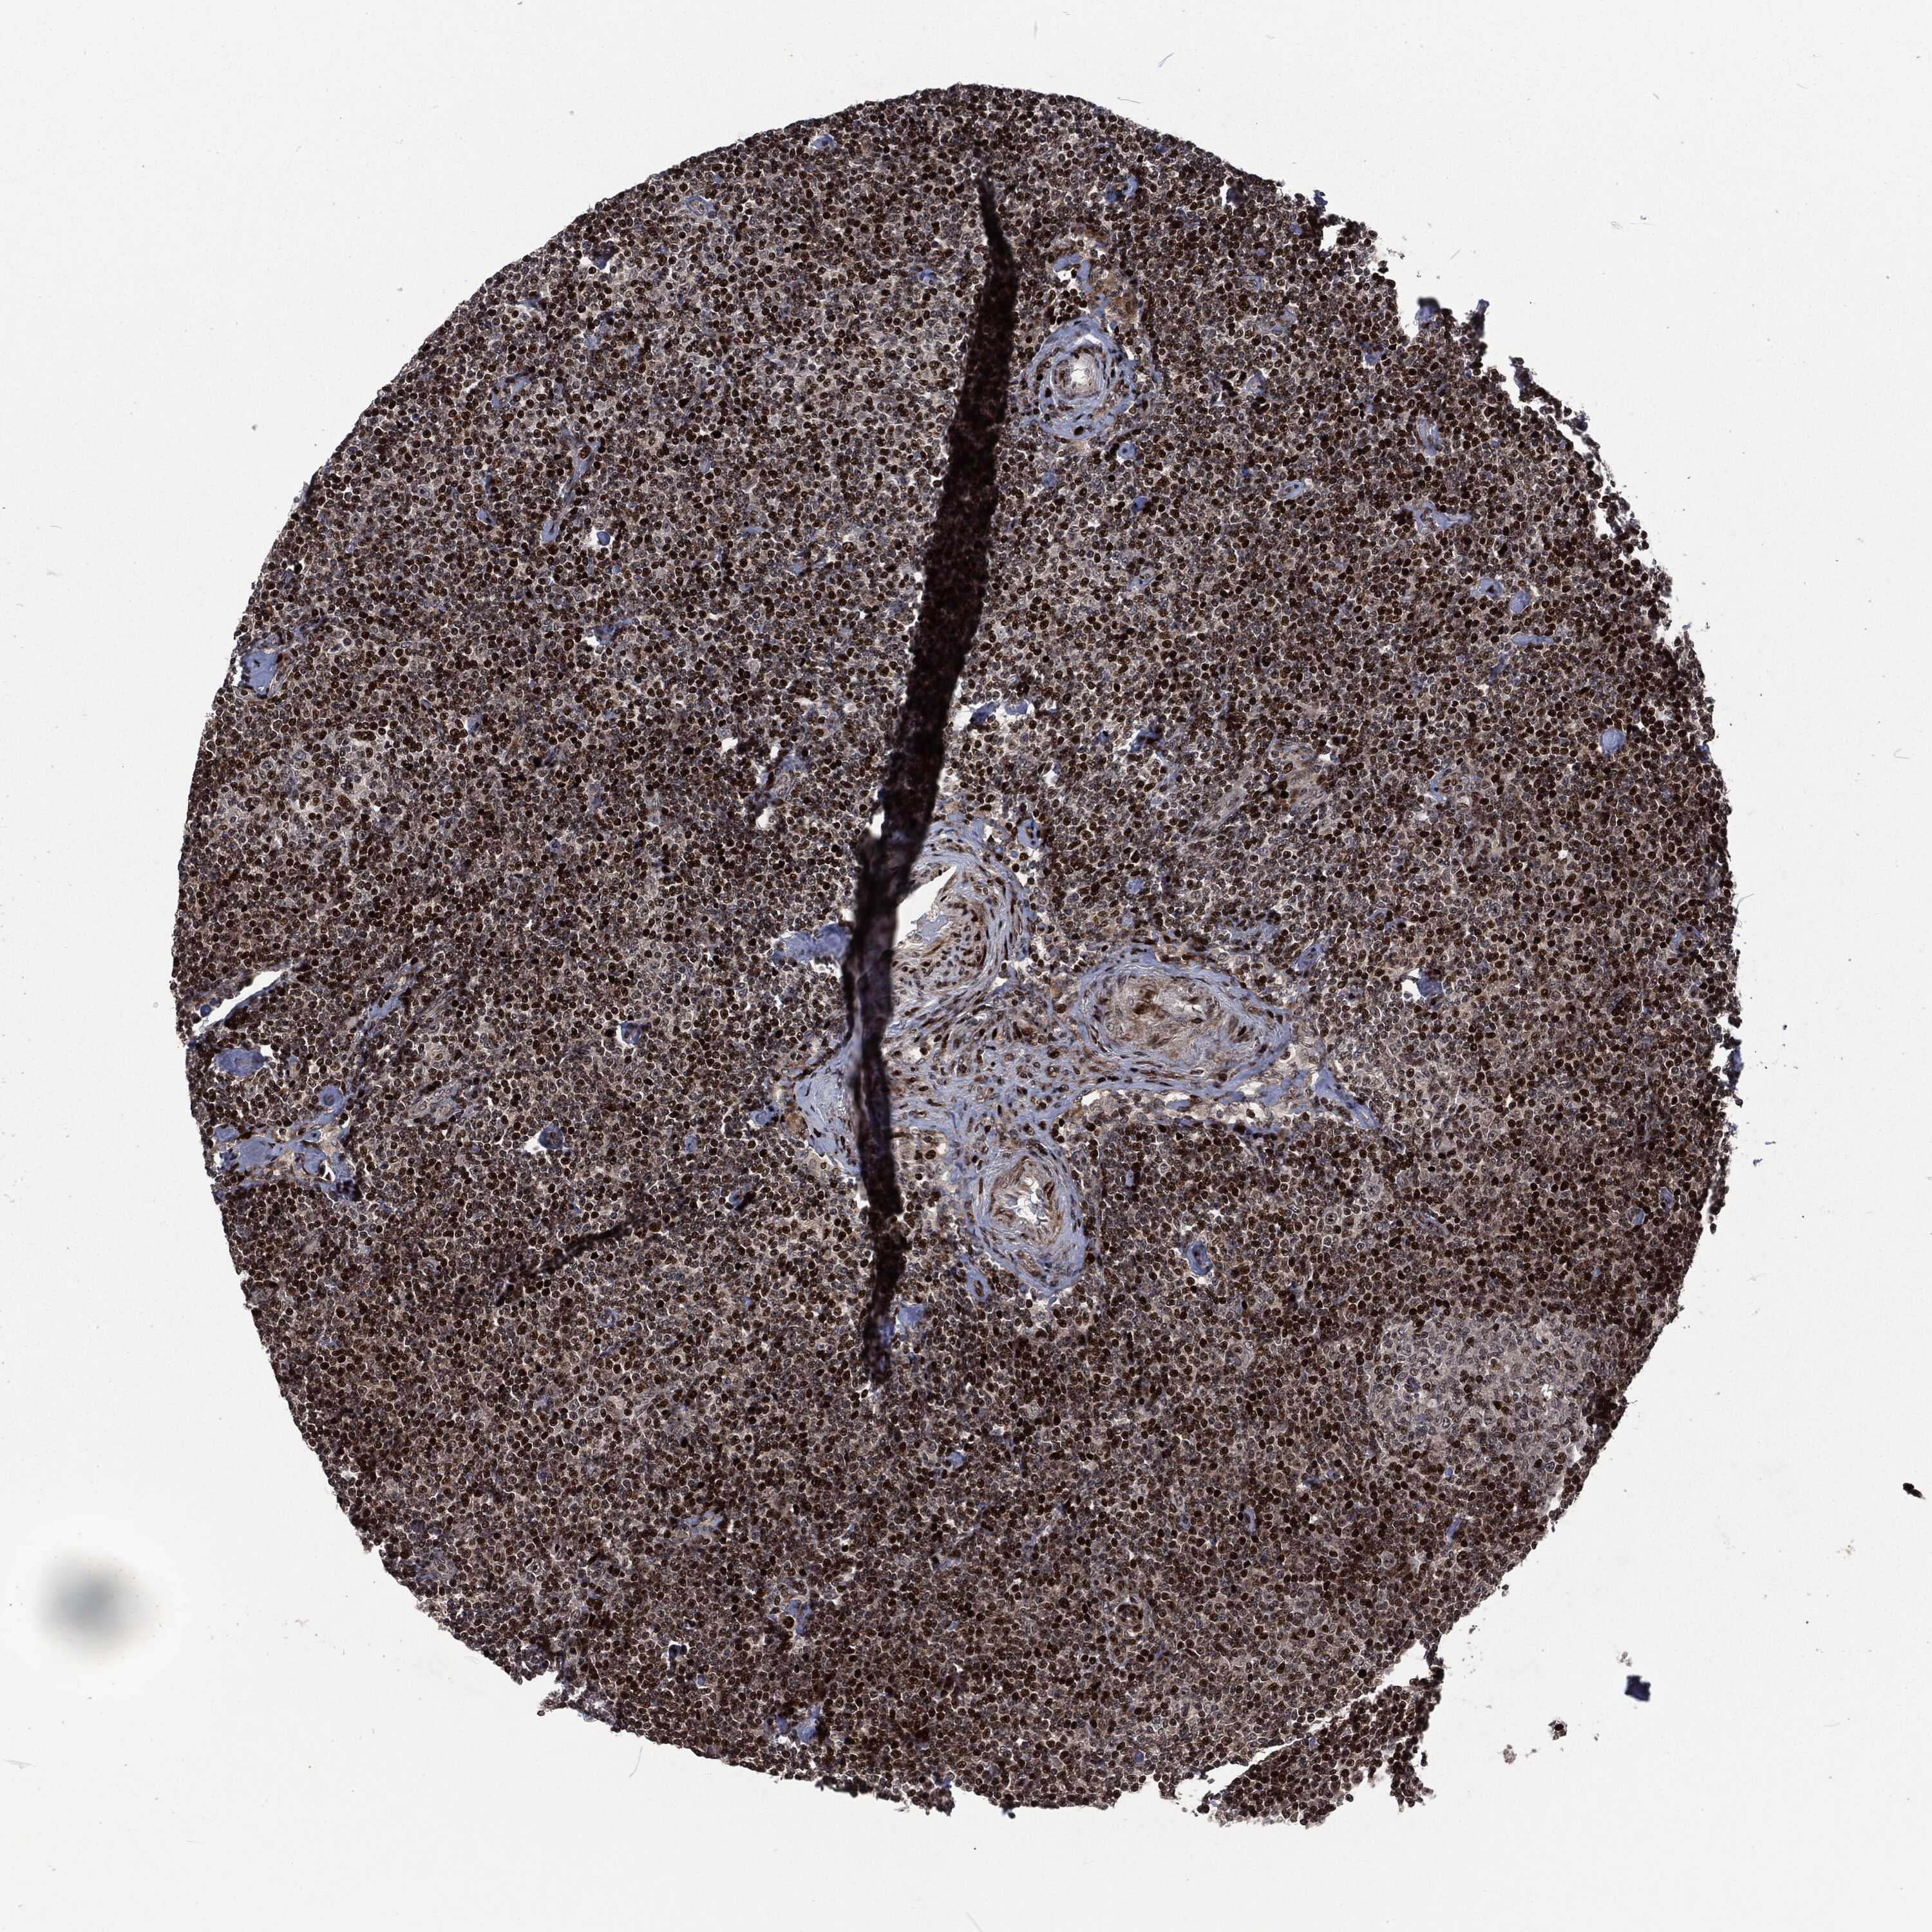

CANCER LYMPHOMA Show tissue menu

LYMPHOMA - Protein expressioni

A mouse-over function shows sample information and annotation data. Click on an image to view it in a full screen mode. Samples can be filtered based on level of antibody staining by selecting one or several of the following categories: high, medium, low and not detected. The assay and annotation is described here.

Each image is clickable and will lead to virtual microscopy that enables deeper exploration of all samples and also displays staining intensity scores, fraction scores and subcellular localization as well as patient and tissue information for each sample.

Malignant lymphoma, non-Hodgkin's type, High grade

Hodgkin's disease, NOS

Malignant lymphoma, non-Hodgkin's type, Low grade